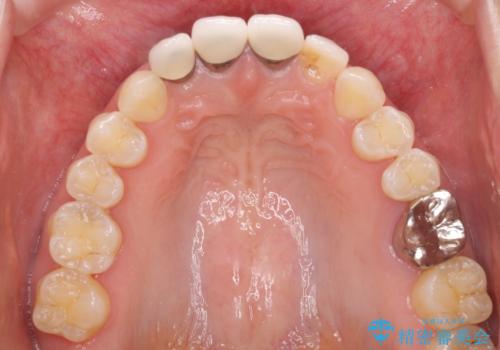

- 上の前歯のセラミッククラウンが古くなったことと、下の前歯のデコボコを気にして来院された患者様です。

前歯は一部根管治療を行った後にオールセラミッククラウンに補綴することとしました。

補綴治療に先立ち、下顎前歯の部分矯正を行い、前歯の咬み合わせの安定性向上を図りました。

当初は上顎の補綴治療のみを希望されていましたが、仮歯装着期間に上下の前歯の接触が気になったため、部分矯正を行うこととしました。